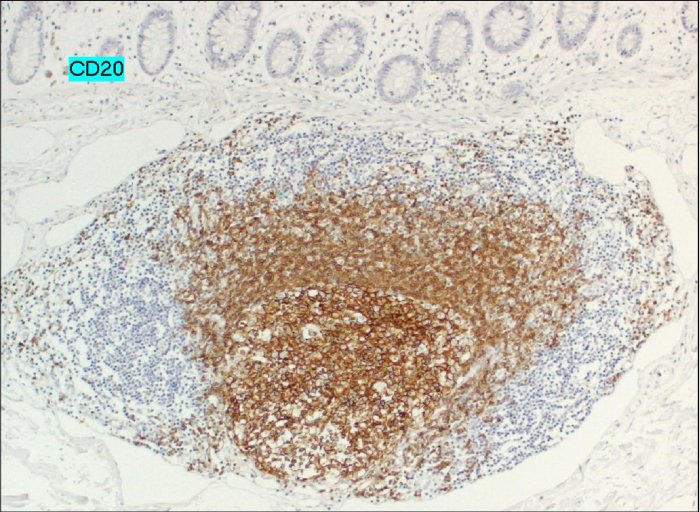

A differenza della forma gastrica, comunque rara, che può associarsi a lesioni ulcerose, questo non si verifica nella forma a localizzazione intestinale. Dal punto di vista istologico i noduli sono costituiti da infiltrato linfoide, composto soprattutto da linfociti B (più raramente linfociti T e plasmacellule) con rare plasmacellule, prominente, confinato alla lamina propria e alla superficie sottomucosa. Nella Figura 3 la reazione positiva per l'anticorpo CD20 dimostra la presenza di linfociti B nell'infiltrato, mentre la negatività dell'anticorpo CD3 conferma che l'infiltrato non è costituito dai linfociti T.